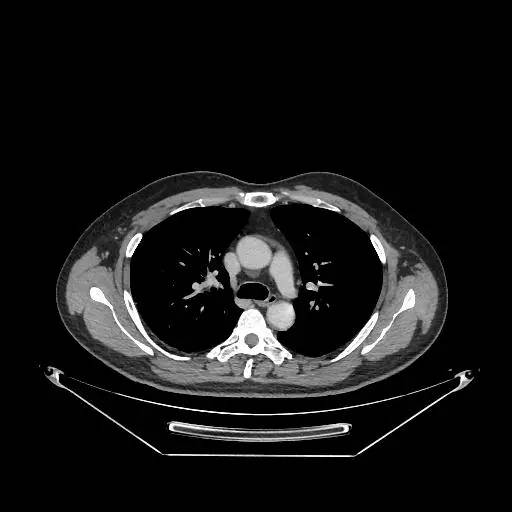

男,47岁,查体发现右肺小结节8月余。

右肺上叶可见直径约7mm磨玻璃样结节,其内见空泡影,有浅分叶及血管集束征象,增强扫描无强化,余肺、纵隔未见明显异常。

右肺上叶不典型腺瘤样增生(AAH)

AAH的影像学特点为呈类圆形小病灶,边界清楚,淡至中等密度均匀的毛玻璃或磨砂玻璃阴影,不遮蔽其下的肺实质,多数在5 mm以下。